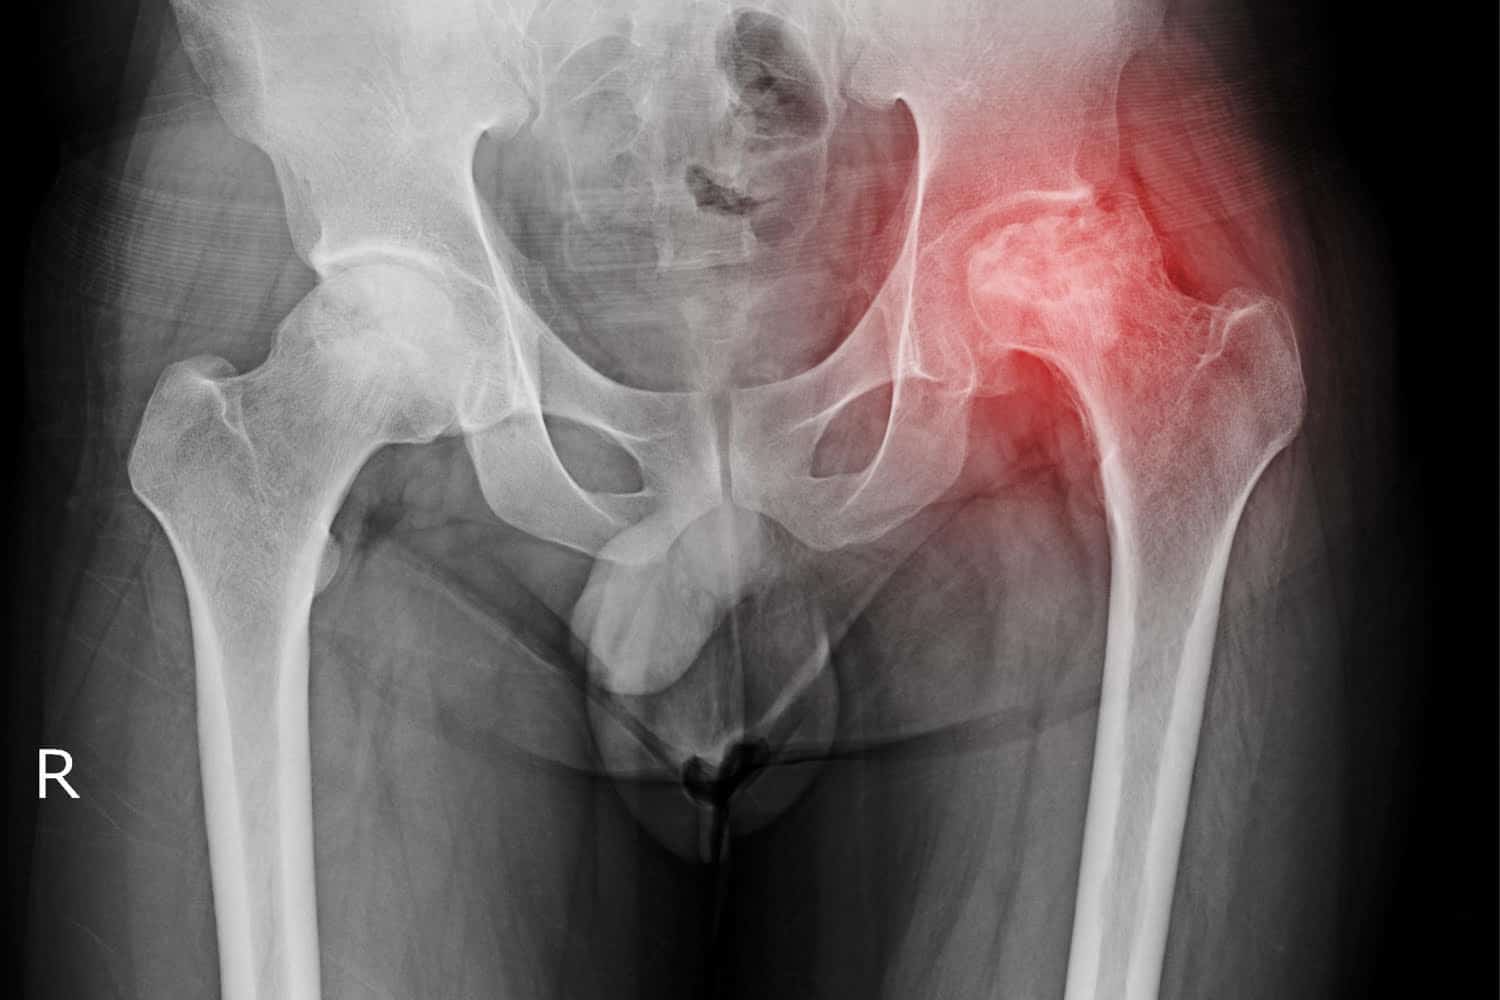

La prótesis de cadera es un dispositivo médico diseñado para reemplazar una cadera dañada. Este procedimiento es común en personas que sufren de dolor intenso o que tienen problemas para moverse debido a enfermedades como la artritis o lesiones graves. La prótesis de cadera permite recuperar la movilidad y mejorar la calidad de vida del paciente.

Foto: Freepik